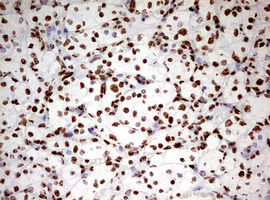

Immunohistochemical staining of paraffin-embedded Human lymphoma tissue using anti-HNRNPM mouse monoclonal antibody. (Heat-induced epitope retrieval by 10mM citric buffer, pH6.0, 120°C for 3min, M06017-2)